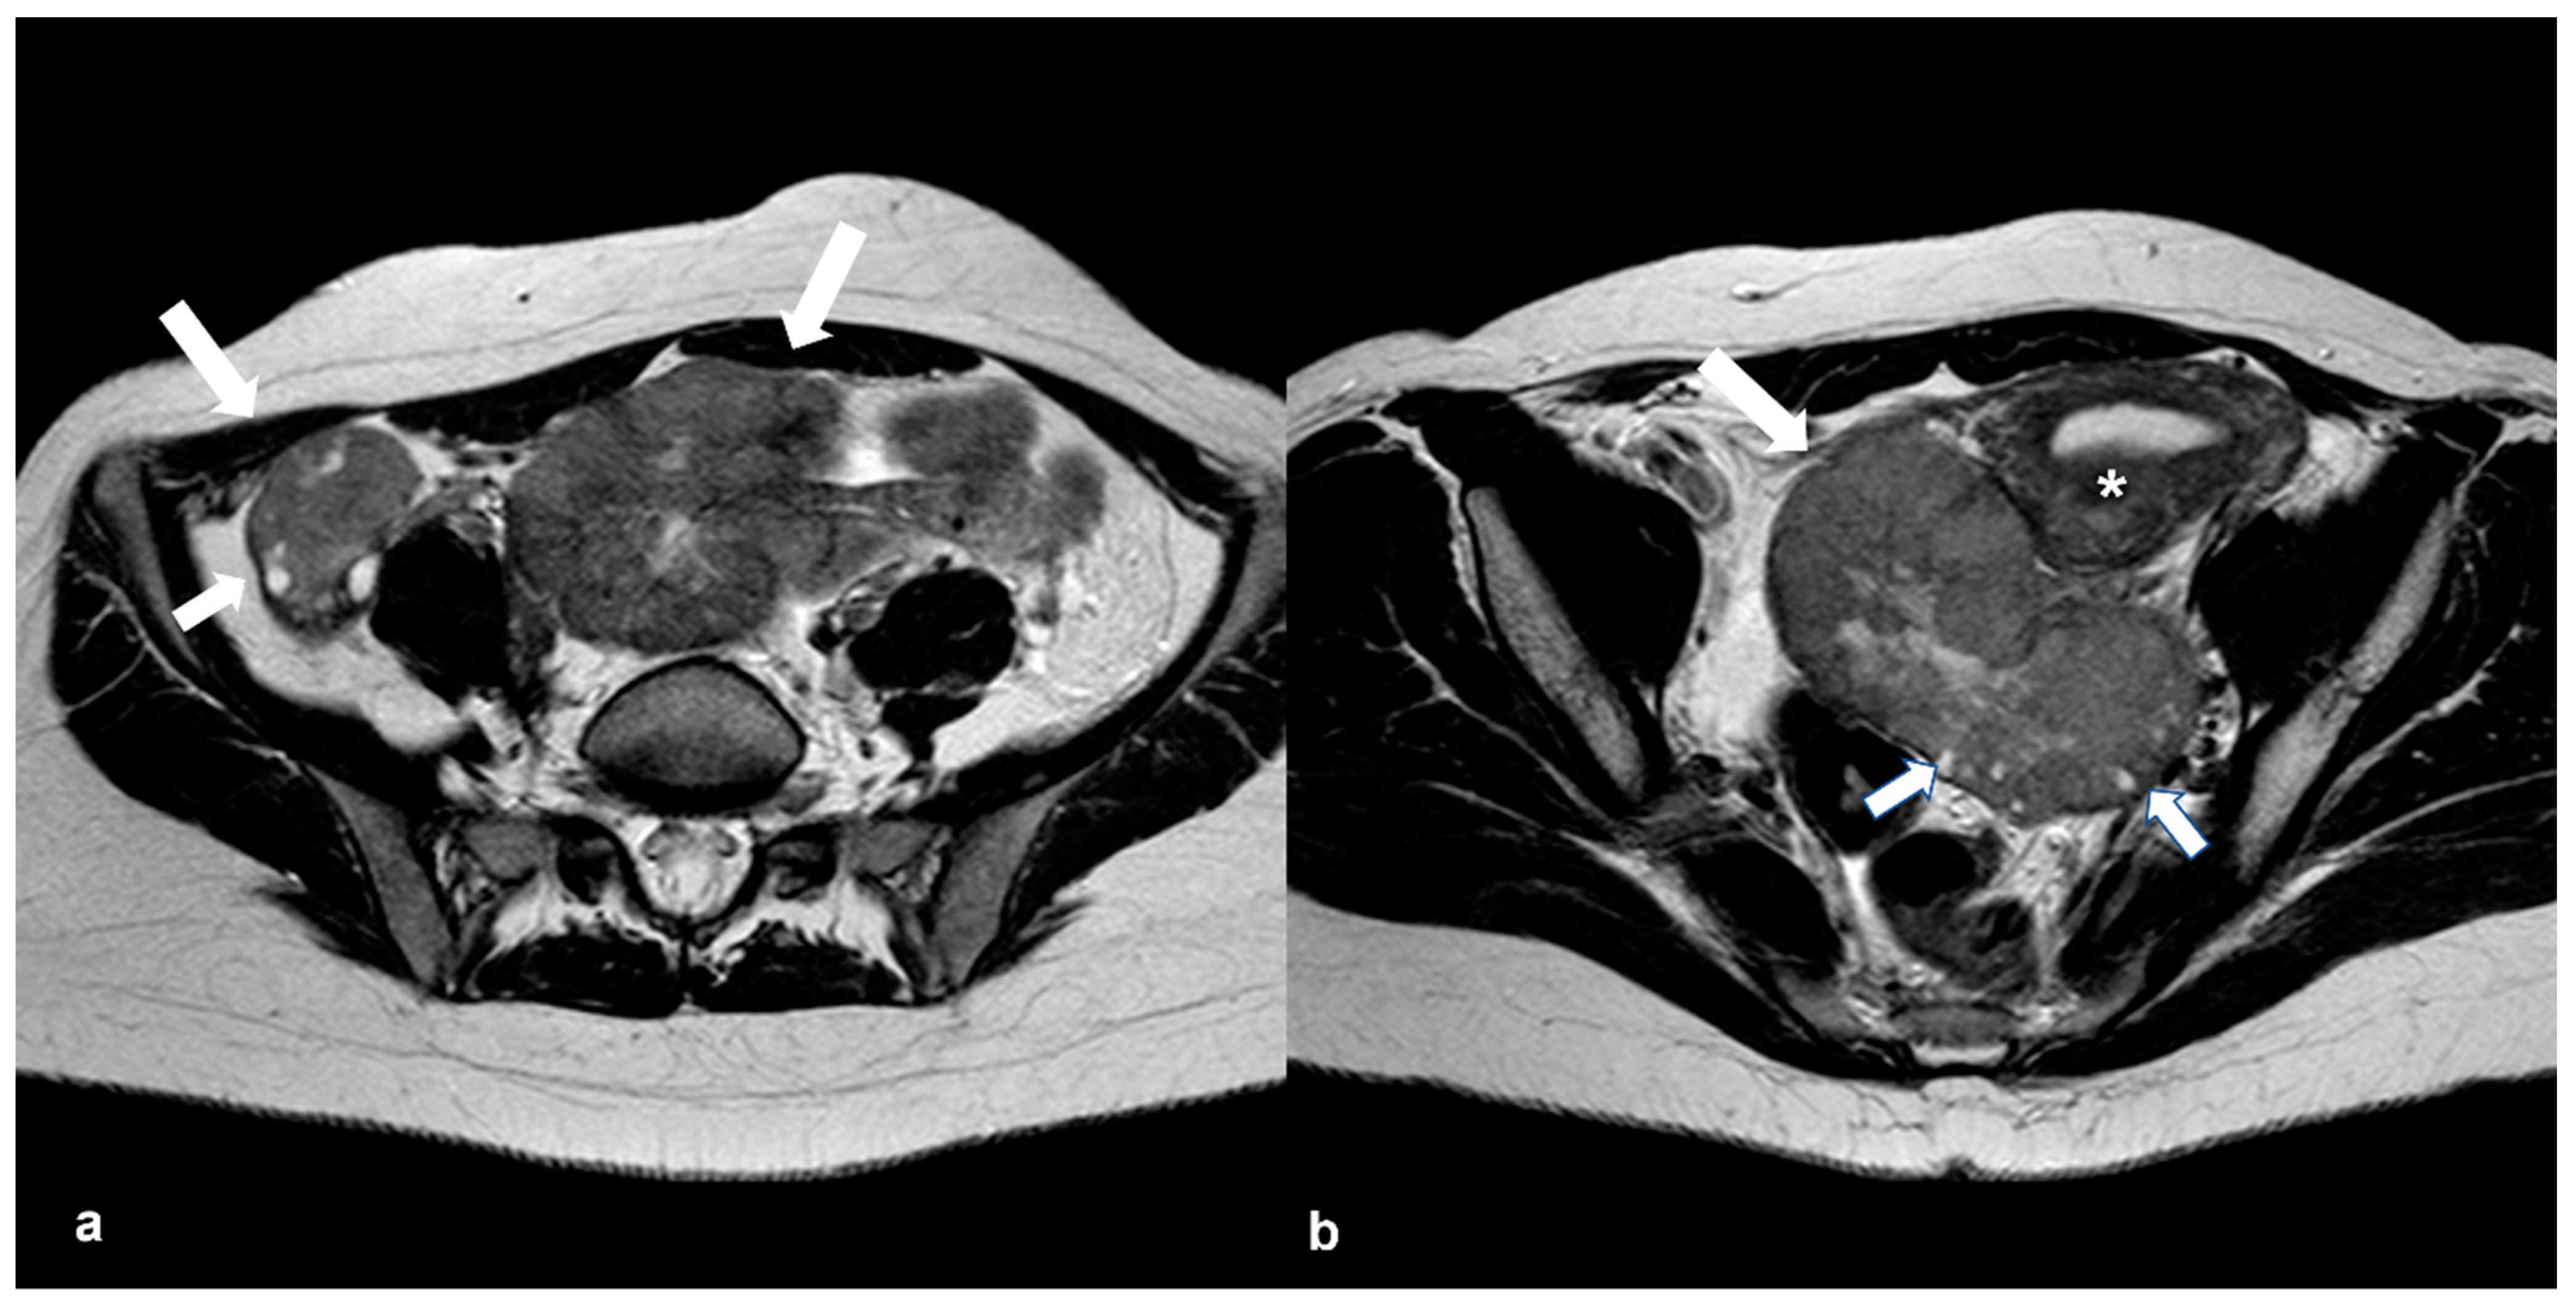

2.1.1. High-Grade Serous Cystadenocarcinoma (HGSC)

2.2. Benign Tumors That Can Mimic EOC

2.2.1. Cystadenofibroma